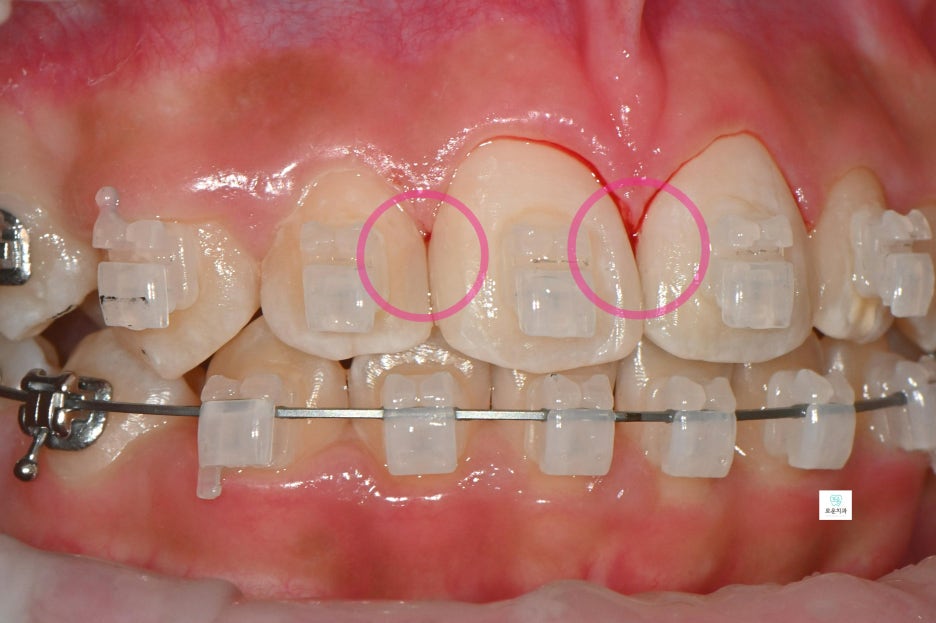

엑스레이 촬영 결과

인접면 충치가 더욱 명확하게 확인되었으며

깊이에 따라 마취 후 치료를 진행했습니다.

충치 부위를 제거한 뒤

자연스러운 색상의 레진으로

깔끔하게 수복하였습니다.